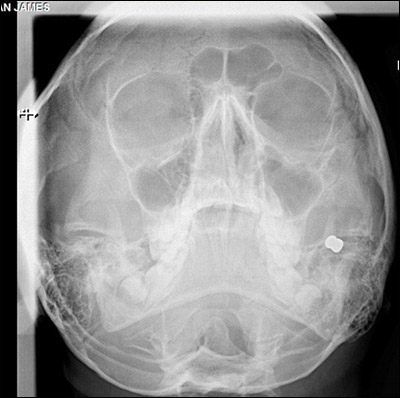

أصيب طالب بريطاني بطلقة نارية في وجهه، الأمر الذي يهدده بالحرمان من التبسم نتيجة لتضرر الأعصاب الرئيسية في وجهه. وكان الصبي "جوردن وينستانلي" (13 عاما) يسير مع مجموعة من أصدقائه عندما أطلق عليه شخص متخفٍ وسط الأشجار النار، فسقط على الأرض والدماء تنهمر من وجهه.

وعلى الفور تم نقله إلى المستشفى حيث خضع لعملية جراحية استمرت 3 ساعات، بحسب صحيفة "ديلي ميل" البريطانية.

وأخبر الأطباء والدي الصبي أنه قد لا يستطيع التبسم بعد ذلك نتيجة لتضرر الأعصاب الرئيسية في خده وفمه، ولذلك تعيش الأسرة حالة انتظار مؤلم لمعرفة إذا ما كان الطفل سيستطيع أن يستعيد ابتسامته أم لا.

وأضافت: "كان من الممكن أن يفقد جوردون عينه لو ارتفعت الرصاصة عدة سنتيمترات فقط. كما كان من الممكن أيضا أن تخترق عنقه، فتؤدي لمقتله.. كان هجوما غير مبرر".